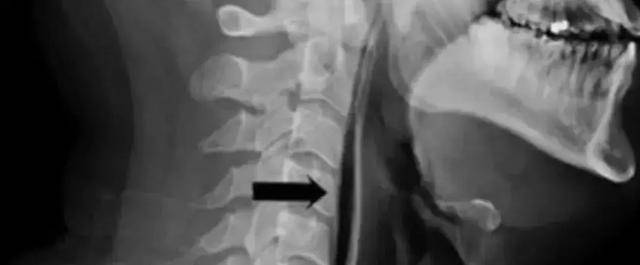

Người đàn ông này đã kiềm chế hắt hơi bằng cách bịt mũi, mím chặt miệng. Kết quả là cổ anh ta đau đớn, khiến anh ta không thể nuốt hoặc nói chuyện. Sau khi thấy tình trạng này kéo dài không có dấu hiệu thuyên giảm, Leicester đã đến bệnh viện kiểm tra và phát hiện yết hầu của anh ta bị sưng.

Sau khi kiểm tra X quang, bác sĩ còn phát hiện không khí rò rỉ từ khí quản của người đàn ông thông qua chỗ bị vỡ và đi vào mô mềm của cổ. Nguyên nhân dẫn đến việc này chính là do hành động nhịn hắt hơi, khiến cổ, khí quản bị vỡ.